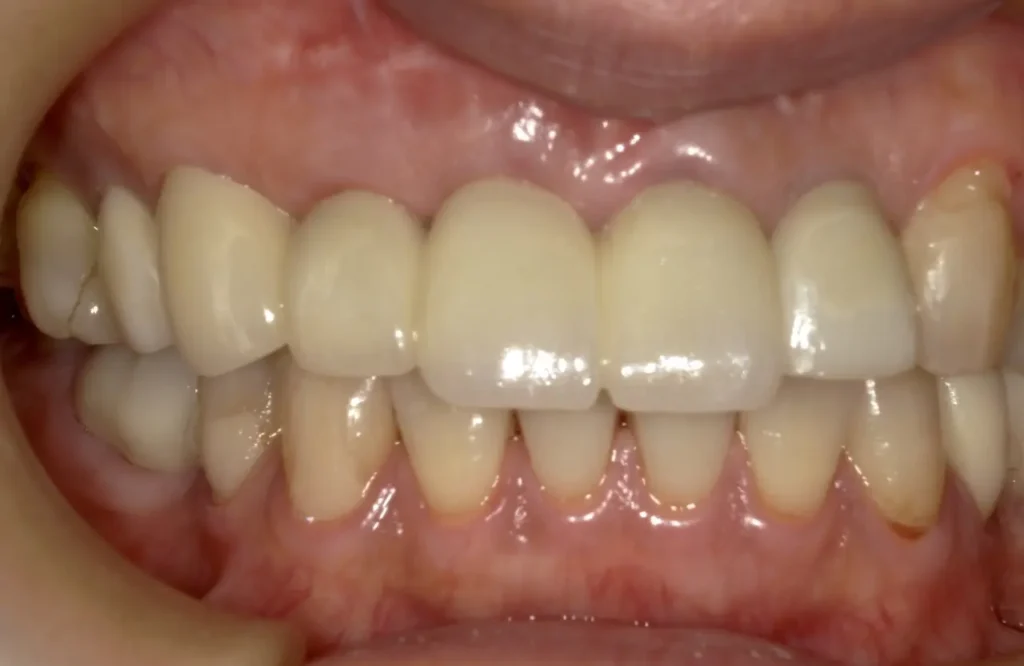

術後1年口腔内写真

ウミの出口もなくなり外科的処置の跡はほとんどなく、被せ物も天然歯と見分けつきません

外科的処置の跡はほとんどなく、ブリッジも自然な感じで歯がないようには見えません